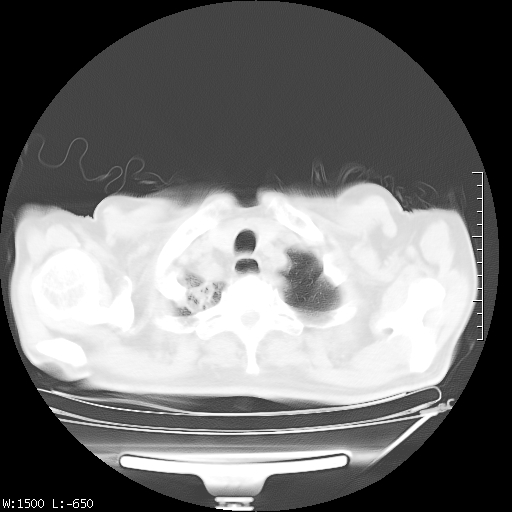

标题: CT23994:男、72、咳嗽、气短两月余,近来消瘦。 [打印本页]

标题: CT23994:男、72、咳嗽、气短两月余,近来消瘦。

右上肺实变,与胸膜关系密切,右肺容积缩小,隆突下淋巴结增大,考虑1 肺结核 2 肺癌

右上肺大片状密度增高影,与胸膜关系密切,内见低密度透亮影,胸膜下可见三角形不张影,左下肺沿支气管走形结节影,纵膈内淋巴结显示。考虑结核并疤痕性不张可能性大,建议穿刺活检,排除肺泡癌。